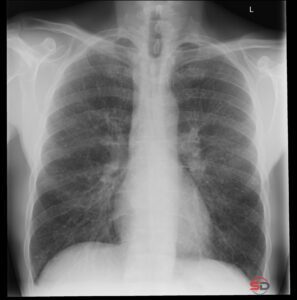

Die atypische Pneumonie ist ein klinisch und radiologisch relevantes Krankheitsbild. Der Begriff ist historisch gewachsen und beschreibt heute vor allem bestimmte Erregergruppen – nicht ein klar definiertes Röntgenmuster. Für die konventionelle Radiologie bleibt das Thoraxröntgen jedoch die zentrale Erstuntersuchung. Dieser Beitrag zeigt, wie sich eine atypische Pneumonie im Röntgen präsentiert und worauf in der Befundung zu achten ist.

Konventionelles Röntgen: Typische Muster

1. Retikulonoduläre Zeichnungsvermehrung

Häufig zeigt sich eine interstitielle Zeichnungsvermehrung mit feinen, unscharfen Verschattungen. Diese können peribronchial betont sein und wirken weniger kompakt als klassische lobäre Infiltrate.

2. Fleckige, multilobuläre Infiltrate

Im Gegensatz zur typischen bakteriellen Pneumonie fehlt oft die scharf begrenzte Lobärstruktur. Die Infiltrate erscheinen:

- unscharf begrenzt

- patchy verteilt

- multifokal

3. Perihiläre oder basale Betonung

Gerade bei viralen Pneumonien finden sich häufig beidseitige, perihiläre Verdichtungen mit interstitieller Komponente.

4. Diskrepanz zwischen Klinik und Röntgen

Ein wichtiger Hinweis ist die klinisch-radiologische Diskrepanz. Patientinnen und Patienten wirken teils deutlich krank, während das Röntgen nur diskrete Veränderungen zeigt.

Die atypische Pneumonie ist primär ein mikrobiologischer Begriff. Im Röntgen zeigt sie häufig interstitielle oder multilobuläre Muster ohne klare Lobärgrenzen. Das Thoraxröntgen bleibt die zentrale Erstdiagnostik. Eine strukturierte Musteranalyse und klinische Korrelation sind entscheidend. Radiologinnen und Radiologen leisten damit einen wichtigen Beitrag zur frühzeitigen Diagnostik und epidemiologischen Einschätzung.